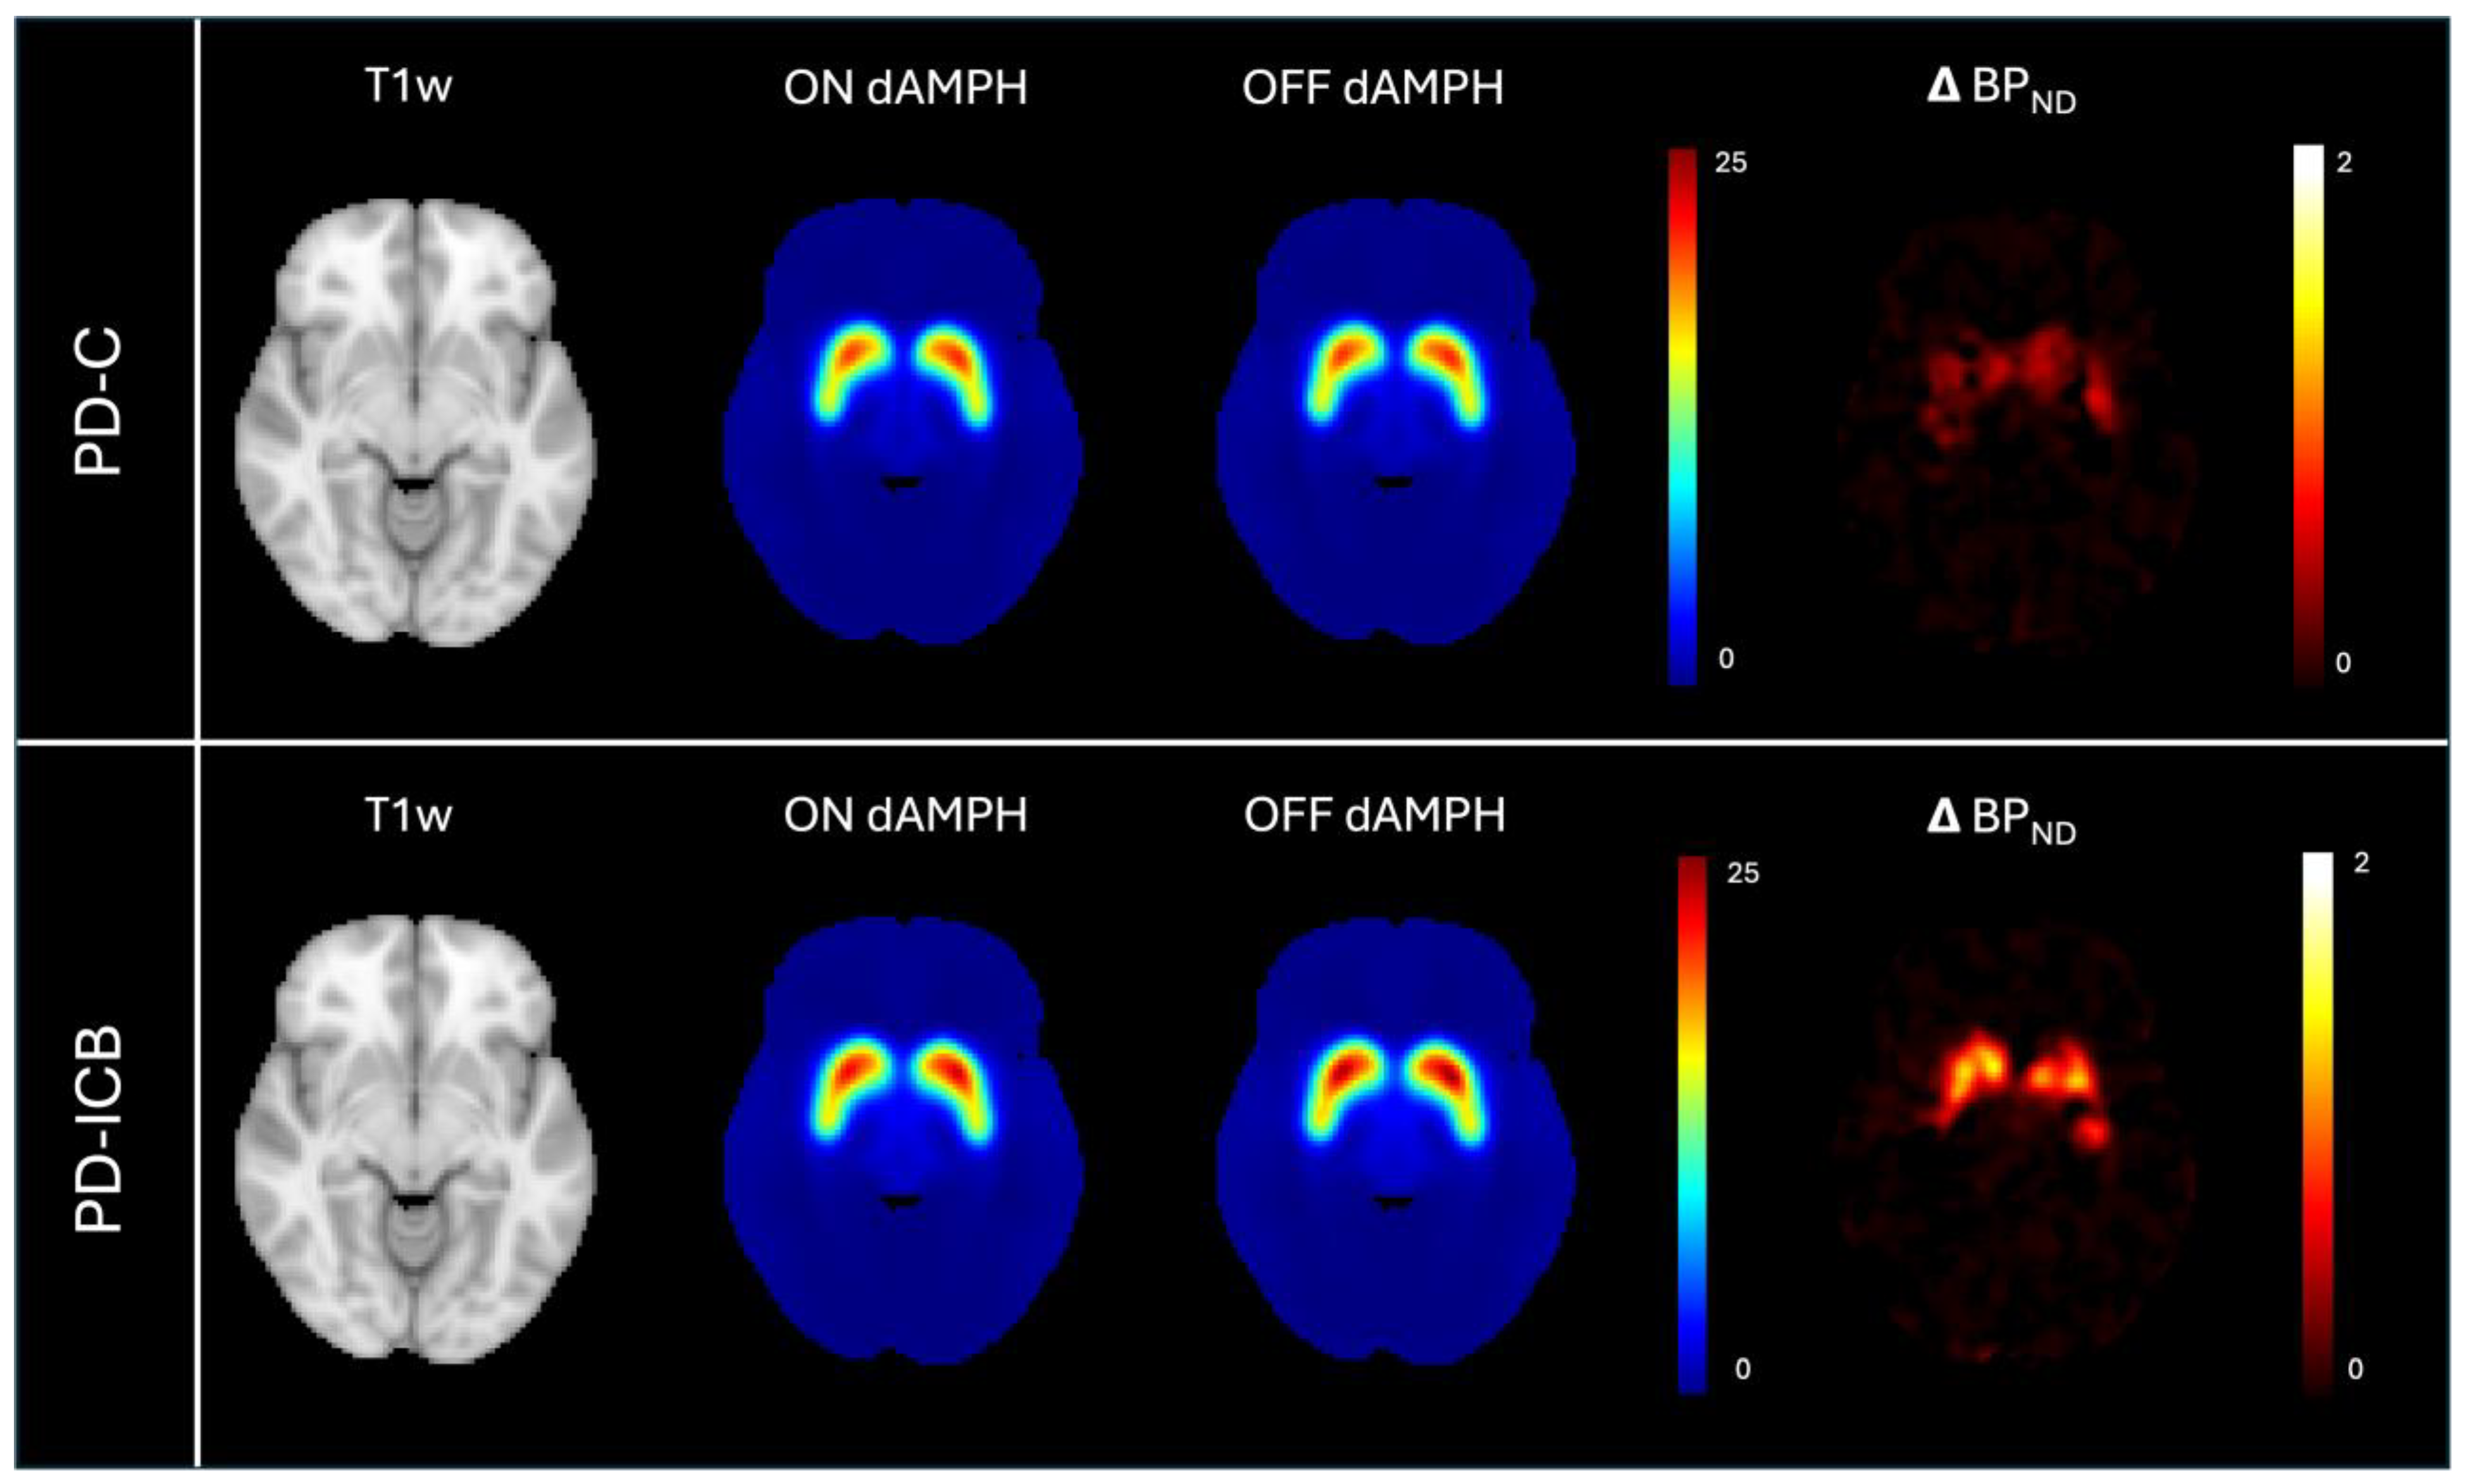

2.2. Localization of DA Release Associations with Subjective Experiences

| PD-ICB | Parkinson’s disease with impulsive–compulsive behaviors |

| PD-C | Parkinson’s disease control |